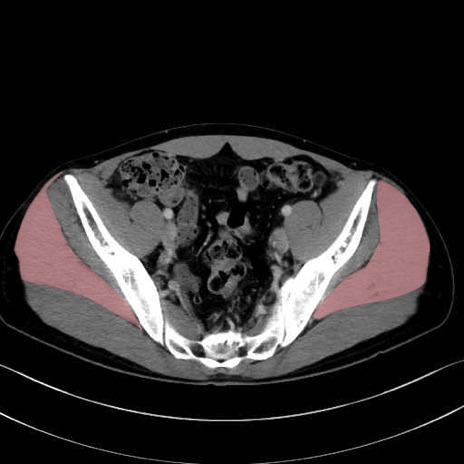

中殿筋 (Gluteus medius)